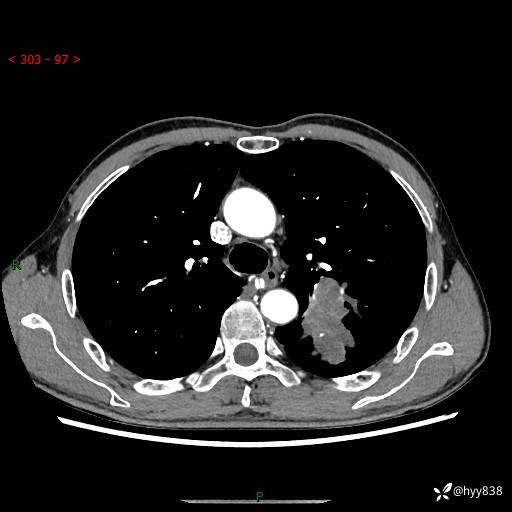

现病史:患者余4月前发现咳嗽咳痰伴痰中带血,无胸闷、胸痛、头晕、恶心、呕吐等不适,2天前因体检发现肺部结节遂于当地市第一人民医院行胸部CT薄层平扫+三维重建示:1.左肺上叶尖后段占位性病变考虑肿瘤性病变伴阻塞性肺炎,右肺上叶后段磨玻璃结节。2.肝内多发囊性灶、左肾结石。现患者为求进一步治疗,于我院门诊就诊,门诊以“肺结节”收入院。 自患病以来,精神、饮食、睡眠尚可,大小便正常,体力体重无明显减轻。

胸部CT增强扫描(外院平扫)